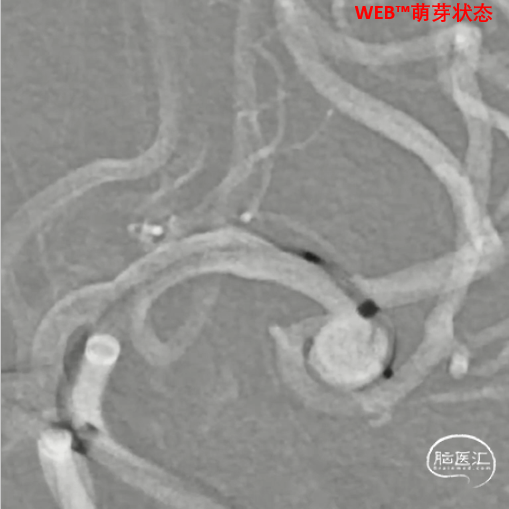

缓慢推出WEB™从种子至萌芽状态,继续向瘤腔内远端缓慢推送WEB™至萌芽至开花间状态;将WEB™和VIA™送至瘤顶,固定WEB™推送杆回撤VIA™,WEB™完全释放。

释放WEB™:缓慢推出WEB™从种子至萌芽状态,继续向瘤腔内远端缓慢推送WEB™至萌芽至开花间状态;将WEB™和VIA™送至瘤顶,固定WEB™推送杆回撤VIA™,WEB™完全释放。